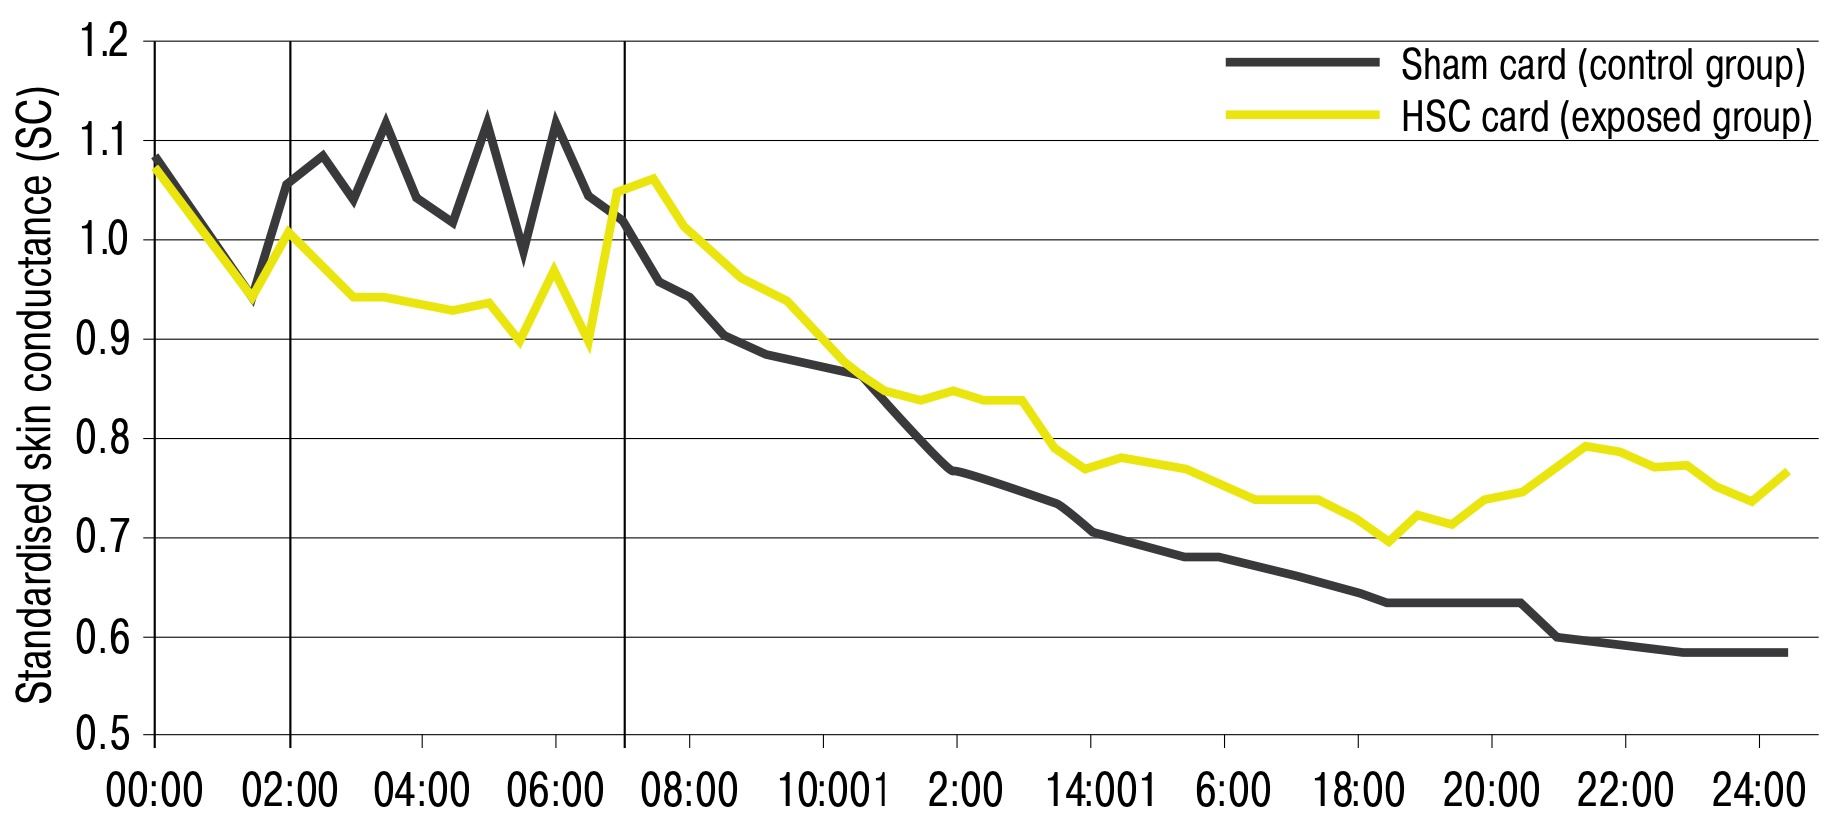

HSC 5G Smart Card

- Etude en double aveugle contre placebo : baisse du stress physiologique avec le HSC 5G Smart Card durant un appel avec un smartphone, remontée plus rapide des niveaux normaux après l'appel, par rapport au groupe placebo. Avec 2 groupes de 12 personnes, l'effet a démontré une différence statistiquement significative pour la température des doigts et la conductance cutanée. La réponse à l'influence protectrice testée de la carte a été très rapide : la différence entre les deux groupes comparés est apparue dès le début de la phase d'appel (zone centrale du graphe, entre 2 et 7 minutes). La conductance cutanée avec HSC était constamment inférieure à celle du groupe témoin pendant la phase d'appel, et l'inverse pour la phase de repos (zone à droite, après 7 minutes). En général, les valeurs de conductance cutanée étaient plus constantes avec HSC, indiquant une influence protectrice. Cela montre qu'appeler avec un téléphone portable sans HSC stresse les participants, tandis que HSC relâche certaines tensions (valeurs inférieures à celles du contrôle). De plus, les participants avec HSC sont plus actifs pendant la phase de repos : l'organisme n'a pas besoin de se reposer après le stress dû au rayonnement subi pendant la phase d'appel, comme c'est manifestement le cas pour le groupe de contrôle.